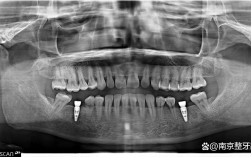

在技术层面,昆山牙博士种牙依托数字化诊疗系统,实现了从检查到手术的全流程精准化,术前,采用德国Sirona CBCT进行三维口腔扫描,生成3D数字模型,精准测量牙槽骨的厚度、密度及神经血管位置,结合口腔美学分析,为患者量身定制种植方案,这种数字化导板技术能将种植误差控制在0.1毫米以内,有效避免传统种植中可能出现的神经损伤、骨量不足等问题,针对不同患者的口腔条件,牙博士提供多种种植技术选择:对于牙槽骨条件较好的患者,采用即刻种植技术,实现“即拔即种”,大大缩短治疗周期;对于骨量不足的患者,通过骨增量技术(如引导骨再生、上颌窦提升等)为种植体提供稳定支撑;针对全口/半口缺牙病例,All-on-4/6即刻负重技术可当天植入种植体并安装临时牙冠,让患者快速恢复咀嚼功能。